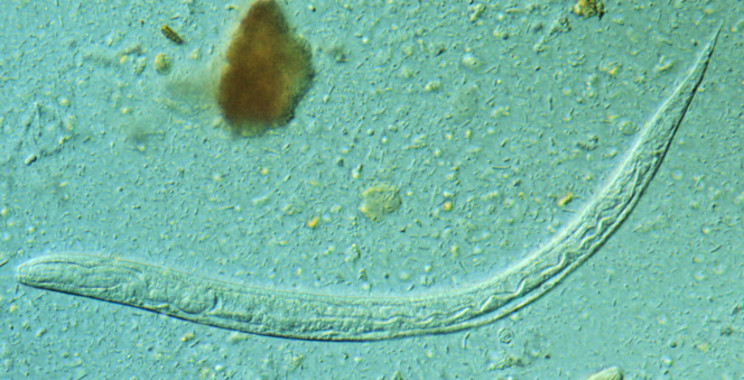

La enfermedad de Chagas (causada por el parásito Trypanosoma cruzi) y la estrongiloidiasis (causada por el helminto S. stercoralis) son enfermedades tropicales desatendidas que comparten una carga epidemiológica similar en Latinoamérica y resultan en infecciones crónicas con alta morbilidad y mortalidad.

En este estudio retrospectivo, los autores buscaron evaluar la asociación entre ambas infecciones en una cohorte de migrantes latinoamericanos atendidos en el Hospital Clinic de Barcelona entre enero 2013 y abril 2015. Los resultados obtenidos a partir de 361 individuos muestran que el 14% de ellos resultó positivo para estrongiloidiasis y el 49% para T. cruzi.

Ser de origen boliviano, proceder de una zona rural y haber vivido en una casa de adobe son factores asociados a la infección por T. cruzi. Un mayor porcentaje de pacientes con estrongiloidiasis estaba infectado por T. cruzi, y viceversa. El análisis estadístico realizado muestra que la infección por T. cruzi se asocia con un riesgo dos veces mayor de padecer estrongiloidiasis en migrantes latinoamericanos que consultan en un servicio de enfermedades tropicales, incluso tras ajustar por otras variables epidemiológicas.